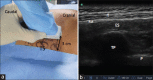

Postoperative pain after breast surgery is difficult to manage owing to its complex innervation. Recently, erector spinae plane (ESP) block, an interfacial block, has been described to provide pain relief after thoracic and abdominal surgeries, multiple rib fractures, and neuropathic thoracic pain. Local anesthetic injected in the erector spinae muscle sheath at the level of the 5th thoracic transverse process is distributed cranially and caudally along the sheath, and to the paravertebral space through apertures in the anterior sheath wall. This may block the dorsal and ventral rami of the thoracic spinal nerves at multiple vertebral levels and the rami communicantes transmitting autonomic fibers to and from the sympathetic ganglia, causing multidermatomal somatic and visceral analgesia. The present case report demonstrates the adequate perioperative analgesia provided by the ultrasound-guided ESP block in patients undergoing various breast surgeries.